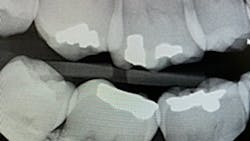

Figure 1 indicates that the PID is not parallel to the interproximal surfaces, causing severe horizontal overlap in both the maxilla and mandible. The radiographic image would be considered undiagnostic. The ideal method used for an excellent bitewing is to have the central beam parallel to proximal surfaces.

Literature suggests using the “open-door method” when contacts need to be clear and diagnostic.5 This method is achieved by moving the sensor distomesially by 15 degrees to ensure the canine is visible. This will keep the interproximal spaces open in the premolar bitewing. To avoid horizontal overlap, the central ray should be perpendicular to the arch of the teeth and directly through the interproximal spaces. With proper training and education on the concepts to mitigate overlapping, we can avoid exposing our patients to unnecessary radiation. Unfortunately, because the angle of the PID is off in Figure 1, the patient will need to be exposed to another radiograph. Proper angulation is shown in Figure 2, and proper positioning of the open-door method is shown in Figure 3.